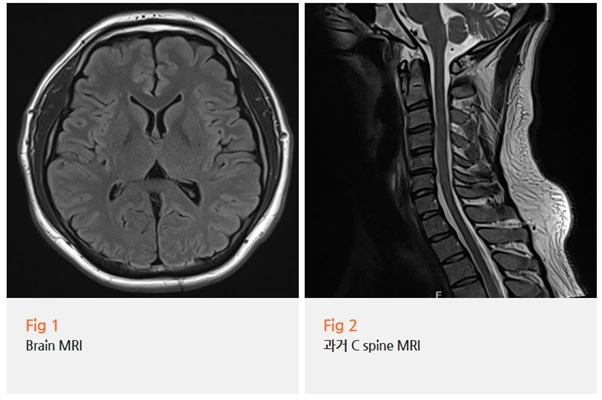

환자분을 안심시켜 드리기 위해 먼저 뇌 MRI를 촬영했어요.

뇌종양이나 뇌혈관 질환 같은 심각한 문제를 배제해야 했거든요.

다행히 뇌 영상은 정상이었어요.

하지만 목 MRI를 자세히 살펴보니

예상대로 상부 경추에 문제가 있었어요.

경추 2-3번 부위의 후관절에 염증 소견이 있었고,

주변 근막과 인대의 긴장도가 상당히 높은 상태였어요.

이런 상태가 지속되면 삼차신경 경로를 자극하게 되고,

결국 눈 주변으로 통증이 느껴지는 거죠.